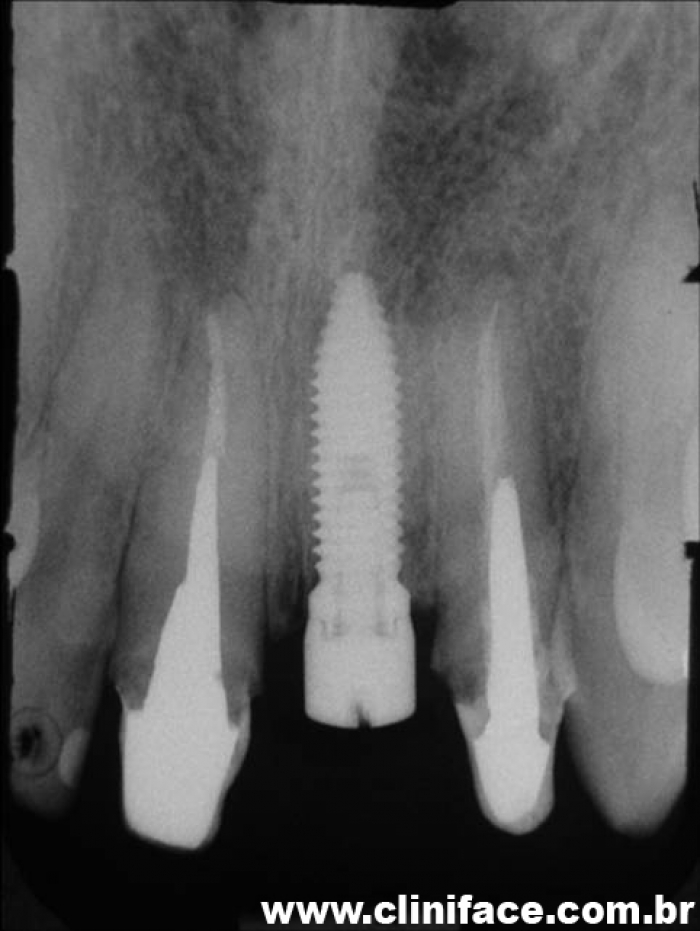

Rx com o implante já instalado

Raio X final